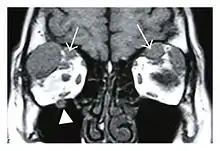

The extent of inflammation that can occur in IgG4-ROD is well demonstrated on magnetic resonance imaging (MRI).

![]() Bilateral supraorbital nerve enlargements (arrows) and right infraorbital nerve (arrow head) enlargement in a 47-year-old woman with a serum IgG4 of 1000 mg/dL.[1] (T1-weighted MRI) |